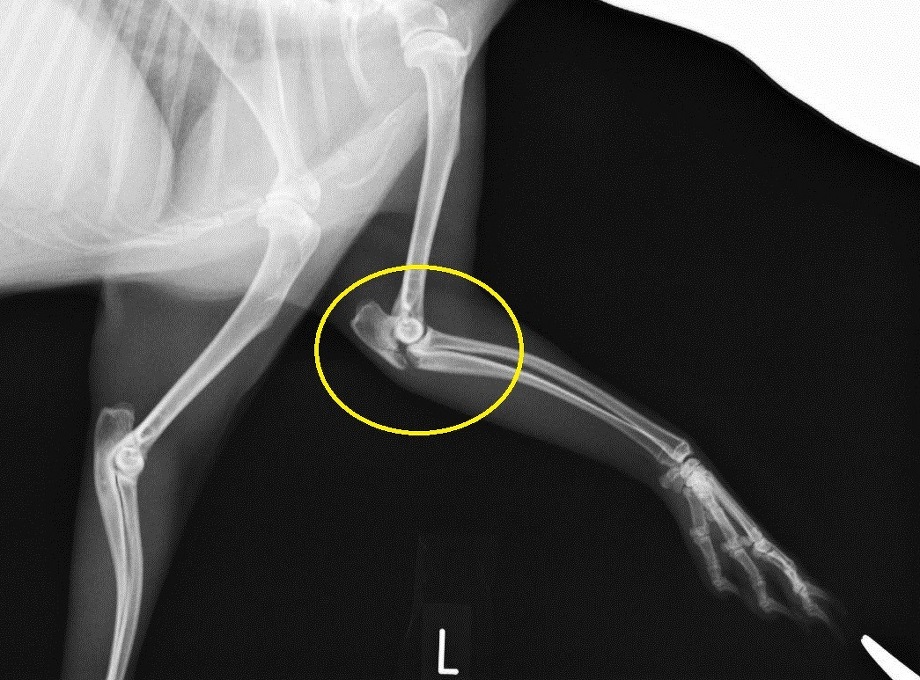

レントゲン撮影をしました。

黄色丸で示した肘頭の部分が骨折しています。

この肘頭の骨折は上腕三頭筋の強力な牽引力で骨片が離断するため、犬ではテンションバンドワイヤーを使用して内固定を実施することが多いです。

しかしながら、ウサギとなると骨密度の薄さからワイヤーで固定しても結局、肘頭部に亀裂が生じて、失敗に終わる経験が過去にあります。